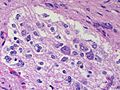

Secondary

Carcinomas:

- Well-demarcated border between brain and lesion - key feature.

- No cytoplasmic processes.

- Usu. have nuclear atypia of malignancy.

- Nuclei often ~3-4x the size of a RBC.

- +/-Glandular arrangement.

- +/-Nucleoli.

| Metastasis | sharp interface with brain, often glandular, +/-nucleoli, no glial processes | often cerebellular, well-circumscribed | usu. old | often suspected to have metastatic disease | TTF-1, CK7, CK20, BRST-2 |